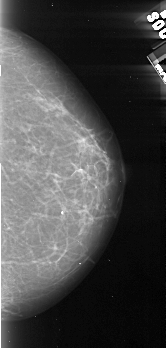

A_1102_1.RIGHT_MLO

RIGHT_MLO LINES 5476 PIXELS_PER_LINE 2071 BITS_PER_PIXEL 16 RESOLUTION 42 NON_OVERLAY